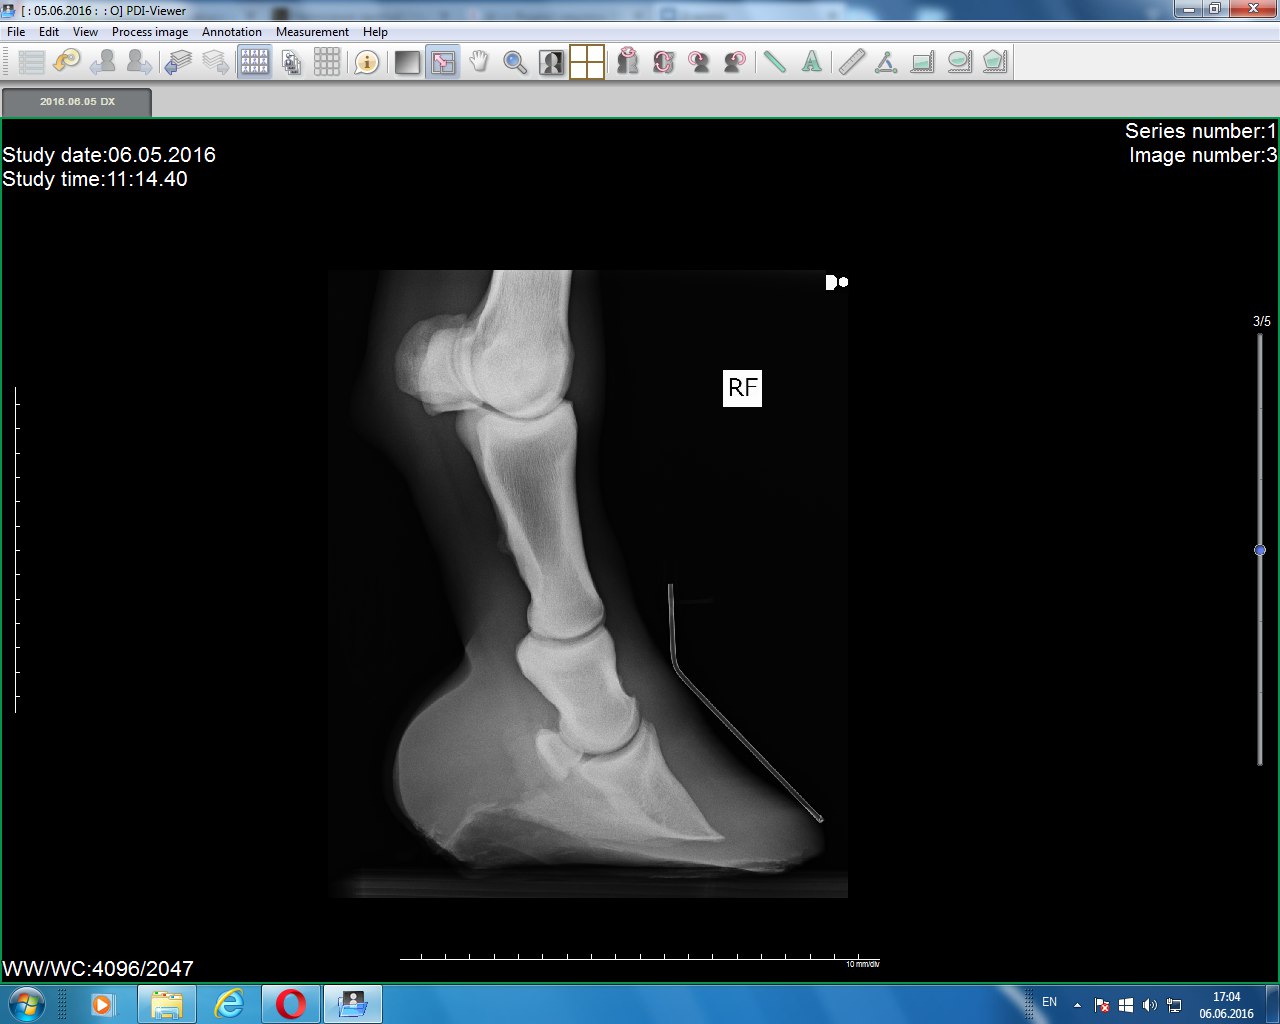

Правый перед(2016) Тут лошадь чуть согнула ногу, потому постав такой странный)